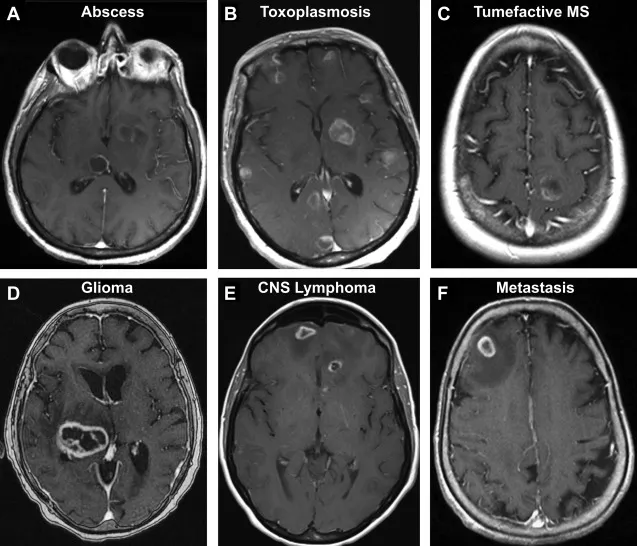

- Brain Abscess:

- CT/MRI: Central area of liquefaction necrosis, surrounded by a thick, enhancing rim and vasogenic edema.

- DWI: Central restricted diffusion is key for pyogenic abscess.

⭐ DWI restriction in the core of a pyogenic abscess is typical.